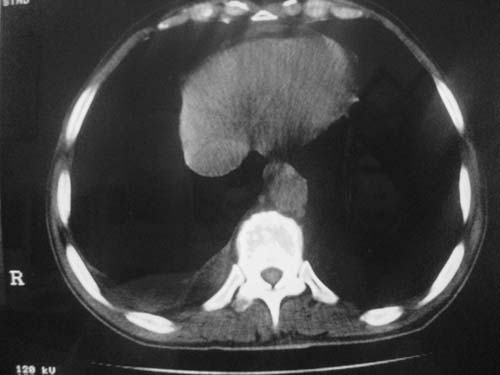

以下是引用科室第一人在2010-3-25 20:30:00的发言:[br]1:纵膈肿瘤性病变,恶性胸腺瘤可能性大伴纵膈右肺门淋巴结转移,右侧胸腔积液。[br]2:右侧肺门肿瘤性病变,纵膈淋巴结转移,右侧胸腔积液。右下叶转移。

以下是引用子期在2010-3-25 21:00:00的发言:[br]先考虑右中央型肺癌伴转移。

以下是引用江广1996在2010-3-25 22:49:00的发言:[br]通常肺癌向纵隔转移多见,纵隔肿瘤向肺内转移少见(有的表现为向肺内侵润)。本例以一元论考虑:右中心型肺癌并纵隔淋巴等多处转移。[br][br][本贴已被 江广1996 于 2010-3-25 22:50:07 修改过]

以下是引用yangyudong333在2010-3-26 6:43:00的发言:[br]“冰冻纵膈”,考虑纵膈淋巴瘤伴肺内及胸膜侵润。